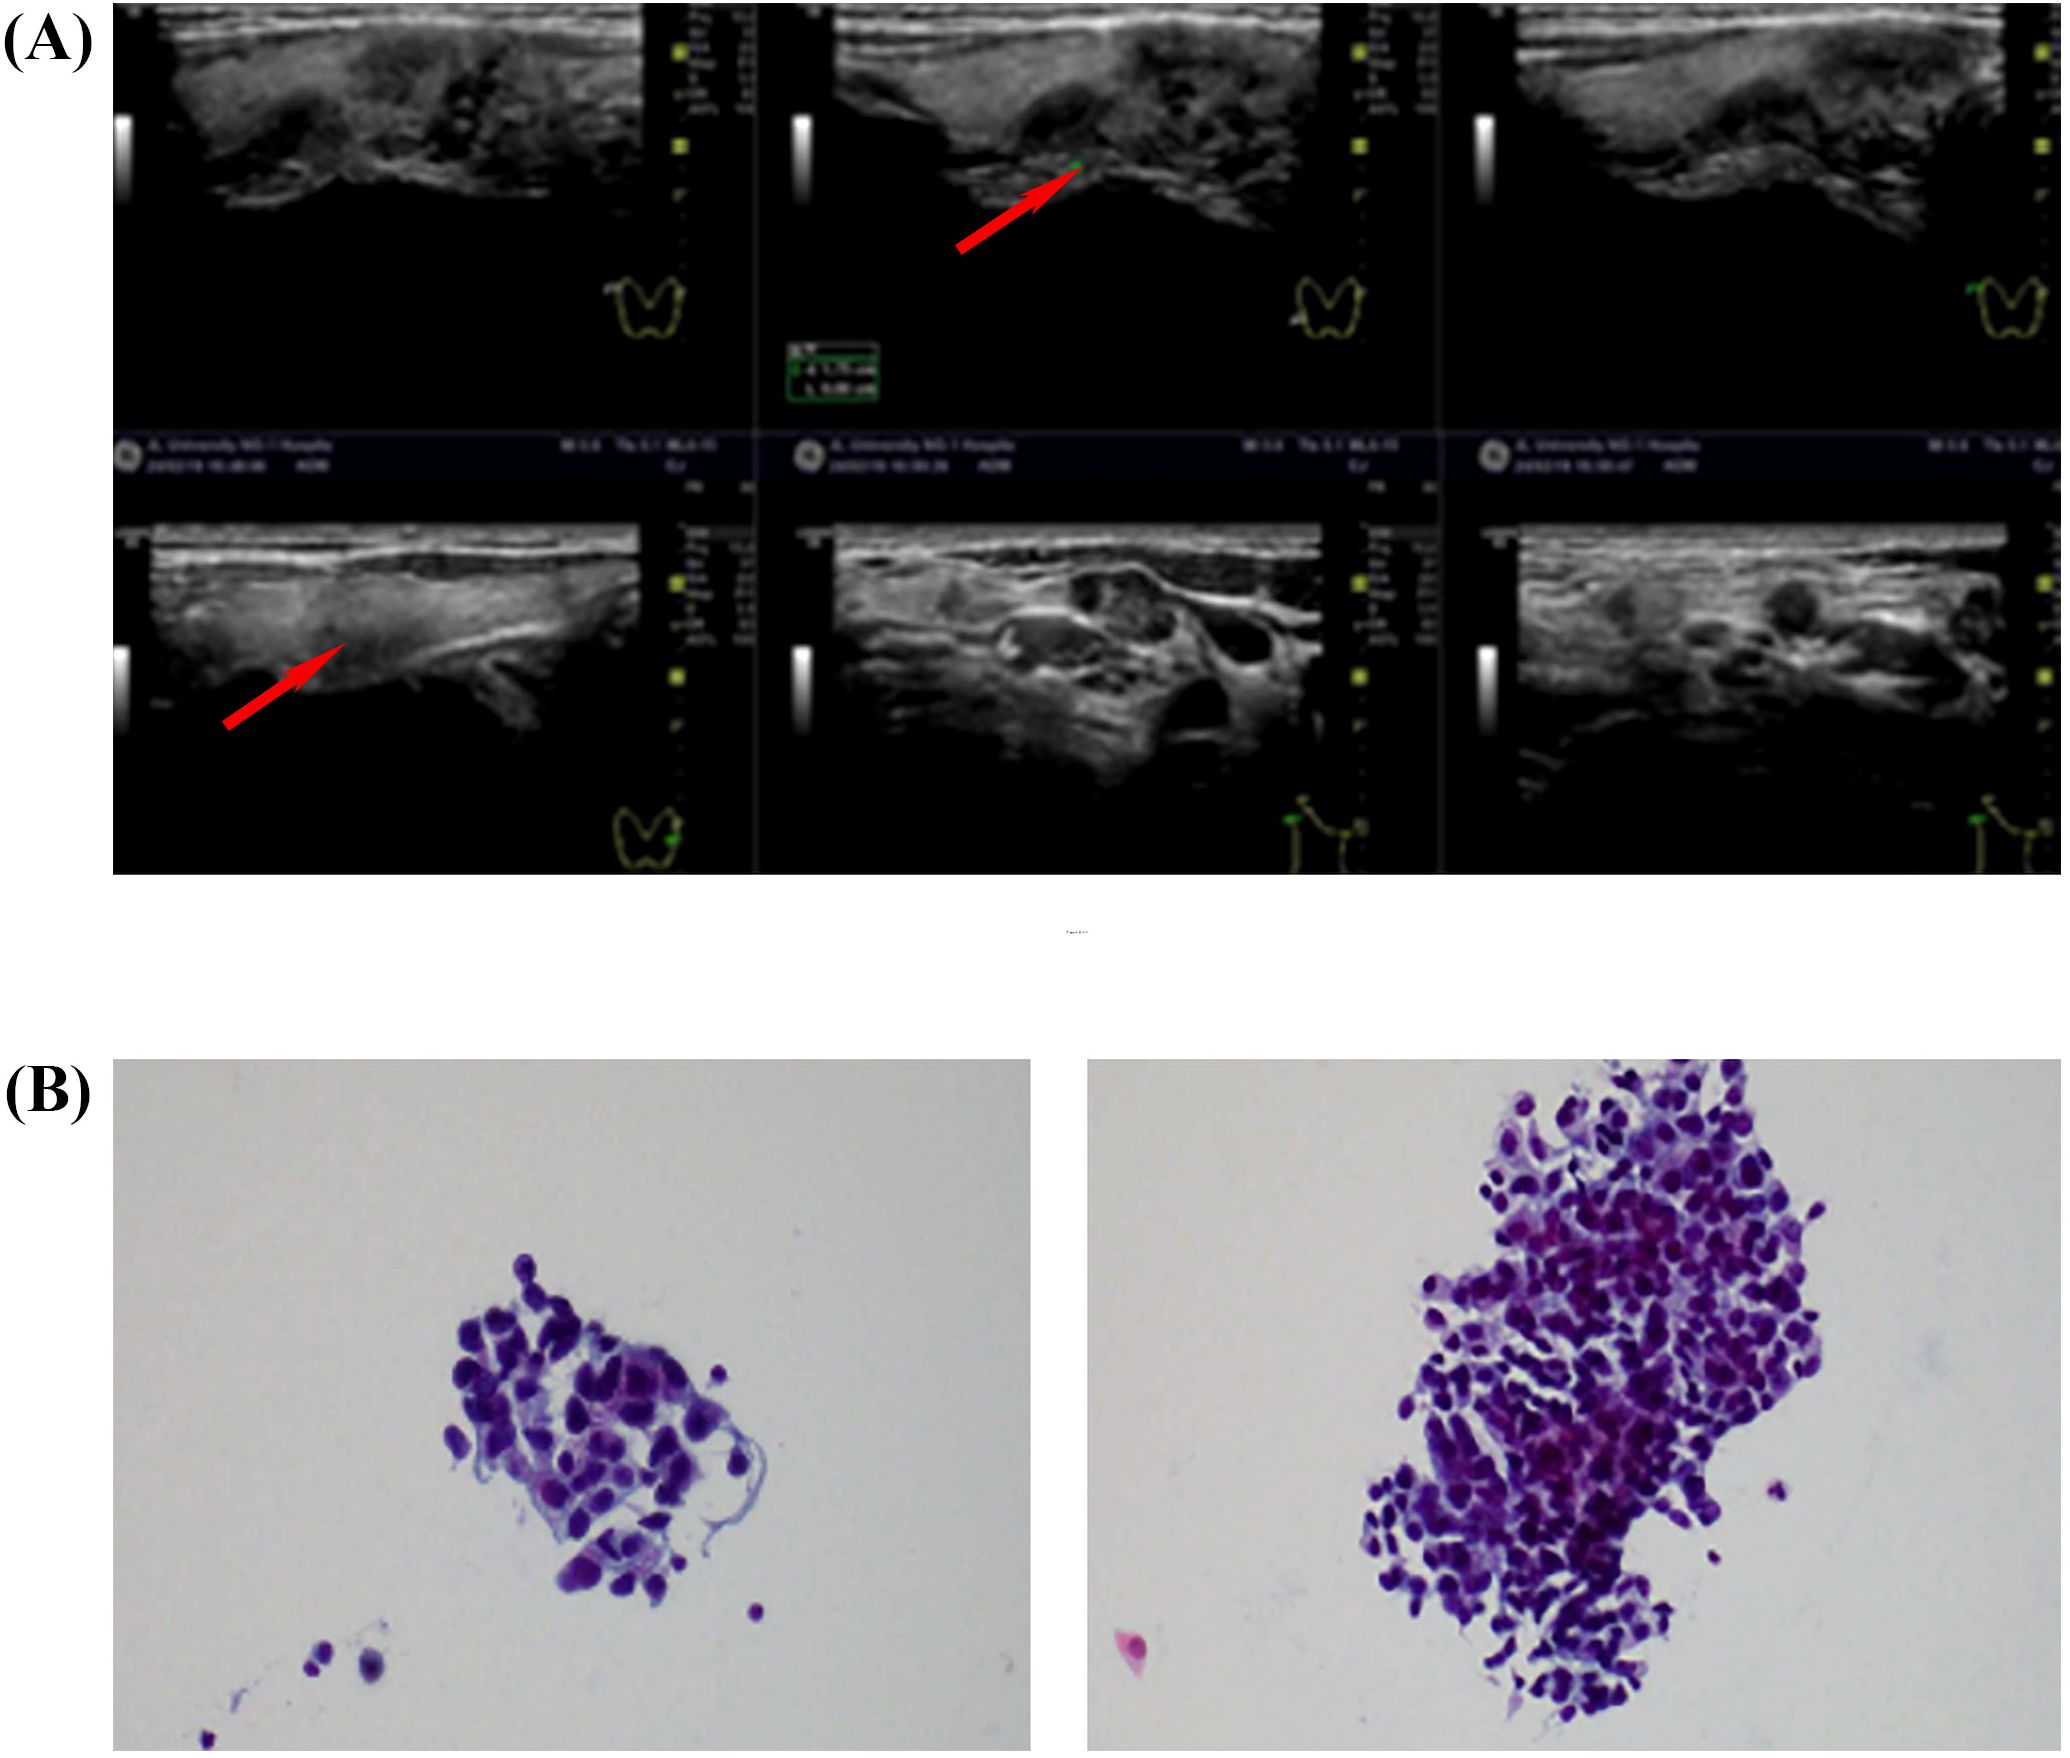

In February 2024, thyroid ultrasound examination revealed multiple nodules in the right thyroid lobe. The dominant nodule, located in the lower pole, measured 10 × 6.4 mm and presented as a solid hypoechoic lesion with ill-defined margins, an irregular shape, and no distinct capsule. Color Doppler flow imaging (CDFI) demonstrated punctate peripheral vascularity around the lesion. Additionally, patchy hypoechoic areas appeared in the right thyroid lobe. The largest lesion, located in the middle portion, measured 15 × 7.6 mm (transverse × anteroposterior), showing ill-defined margins, irregular contour, and heterogeneous internal echogenicity, with minimal vascularity on CDFI. Multiple hypoechoic lymph nodes appeared in the right cervical regions (levels II, III, IV, and V). The largest lymph node at level IV measured 13 × 7 mm and exhibited well-defined margins, irregular cortical contour, and partial fatty hilum effacement. The dominant thyroid nodule was categorized as C-TIRADS 4B (moderate malignancy suspicion), while other nodules were assigned C-TIRADS 3 (low suspicion) based on their overall sonographic presentation(Figure 2A). FNAC of the right thyroid lobe revealed atypical epithelial cells, suggesting possible papillary thyroid carcinoma (PTC). FNAC of the right level IV cervical lymph node identified metastatic carcinoma cells, morphologically suggestive of PTC (Figure 2B). The measurement of thyroglobulin in the aspirate fluid was 0.96 ng/ml, which is below the normal reference range.

(A) Six ultrasound images showing tissue structures, with red arrows indicating specific areas for examination. The images appear to be from a medical diagnostic procedure. (B) Two microscope slides displaying clusters of purple-stained cells, possibly analyzing cellular composition or abnormalities. The slides focus on cell morphology and arrangement.

Figure 2. (A) Thyroid and regional lymph node color Doppler ultrasound (19 February 2024). (B) FNAC of thyroid and lymph node lesions. Smear from the right thyroid lobe (left). Aspirate from a right cervical level IV lymph node (right).